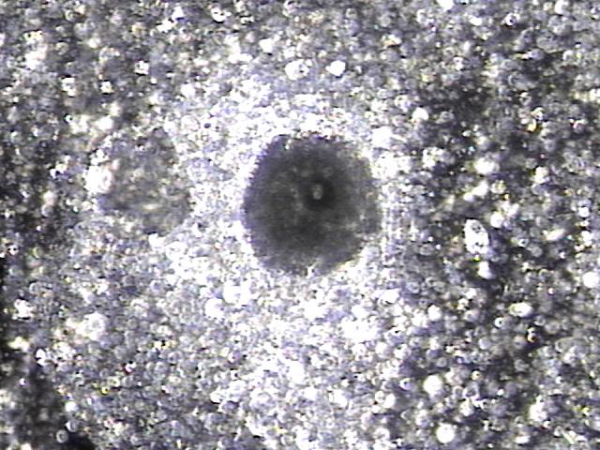

내원 당일 전립선의 표적 치료후 배출된 전립선액의 배양과 PCR 검사를 한후 현미경학적 검사상 치료된 사정관 결석과 전립선의 결석 자료입니다.

On the day of the visit, following targeted prostate treatment, prostatic fluid was discharged and analyzed through culture and PCR testing. Microscopic examination revealed treated ejaculatory duct stones and prostatic calculi.

전립선과 사정관 그리고 사정관입구의 결석 치료중 사정관의 좁은 입구와 전립선관의 막혀 있는 입구로 커다란 결석이 배출시 압력으로 좁아져 있거나

막혀 있던 섬유화된 입구의 손상이 예상되는 현미경학적 사진입니다.

This is a microscopic image taken during the treatment of stones in the prostate, ejaculatory ducts, and the ejaculatory duct orifices.

It shows that large stones being expelled through the narrowed or obstructed fibrotic openings of the ejaculatory and prostatic ducts likely caused mechanical damage due to pressure during expulsion.